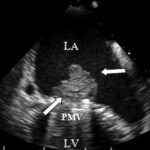

- A qualidade da imagem importa! Em situações em que os parâmetros não são avaliados de forma confiável, quando a imagem for sub-ótima, estes não devem ser levados em consideração;